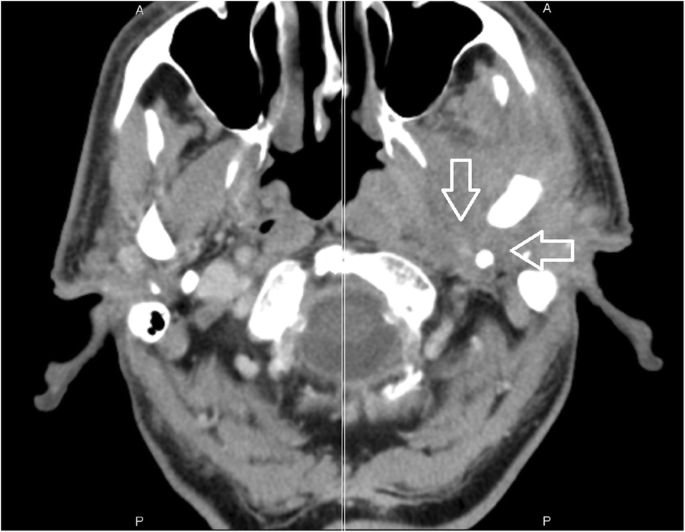

49+ Posterior Belly Of Digastric Ct Background. The digastric muscle (also digastricus) (named digastric as it has two 'bellies') is a small muscle located under the jaw. Venter posterior musculi digastrici) is the largest of the two bellies of the digastric muscle, and it develops from the second pharyngeal arch.

The digastric muscle is one of the suprahyoid muscles. The posterior belly originates from the mastoid notch medial to the mastoid process on the temporal bone. Posterior belly of digastric, venter posterior musculus digastrici.

The digastricus (digastric muscle) consists of two fleshy bellies united by an intermediate rounded tendon. Farlex partner medical dictionary © farlex 2012. All three levels are bounded posteriorly by the posterior edge of sternocleidomastoid muscle (scm). The digastric muscle is one of the suprahyoid muscles.